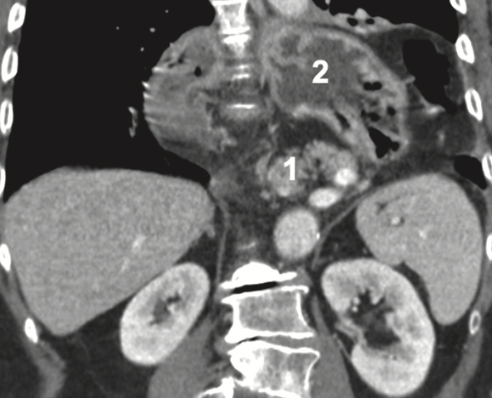

Discusión: Las hernias hiatales paraesofágicas tipo IV suelen contener todo el estómago, colon transverso, epiplón, a veces intestino delgado y más raro el bazo. En la hernia hiatal masiva (HHM) a los órganos señalados se suman el duodeno, la vía biliar y el páncreas. La HHM es de rara ocurrencia y constituye un desafío quirúrgico. La literatura reporta algo más de una treintena de casos en los últimos 50 años casos, no todos operados. El manejo debe ser quirúrgico y precoz, a fin de restaurar prontamente la anatomía y realizado por un equipo con experiencia en el manejo de hernias hiatales complejas.